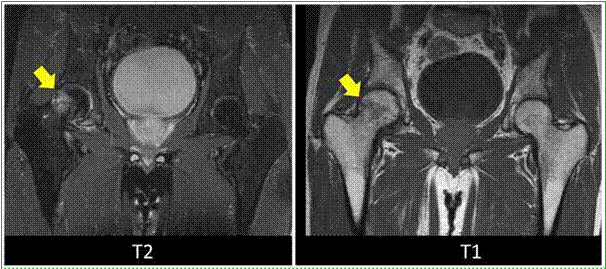

Figura 6. Resonancia magnética en secuencias T2 y T1, corte coronal. El sector subcondral periférico de la cabeza femoral derecha muestra alta señal en secuencia T2, sugestivo de edema óseo compatible con una fractura por insuficiencia en una paciente con osteopenia.